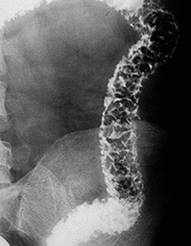

Leziunile endoscopice precoce sunt reprezentate de ulceratiile aftoide. In evolutie apar ulceratii de forma si talie diferita (serpiginoase, in harta geografica sau rotunde). In stadiile avansate apare aspectul caracteristic de "piatra de pavaj" datorita ulceratiilor profunde, confluente, care delimiteaza intre ele insule de mucoasa non-ulcerata. La colonoscopie mai pot fi stenoze frecvent ulcerate. Distributia segmentara, discontinua si asimetrica a leziunilor este o caracteristica endoscopica a bolii Crohn.

Ulceratii aftoide Ulcer map-like, cu stenoza Aspect "piatra de pavaj"

Localizarea leziunilor este exclusiv la nivelul intestinului subtire in 25-30% din cazuri, ileo-colica in 40-50% din cazuri si strict colonica in 15-25 % din cazuri, in special la batrani. Localizarea perianala (fisuri, fistule, abcese, supuratii perirectale) apare in peste 50% din cazuri. In 0,5- 4 % din cazuri pot fi afectate segmentele proximale ale tractului digestiv (cavitatea bucala, esofag, stomac, duoden). Foarte rar boala se poate localiza la apendice.

Examenul baritat cu dublu contrast evidentiaza ulceratiile aftoide sub forma unor mici depozite de substanta de contrast inconjurate de un halo transparent. Mai pot fi evidentiate leziuni unice sau multiple despartite de zone sanatoase- aspectul de "pietre de pavaj", stenoze pana la "semnul sforii", fistule. Cand exista suspiciunea de stenoza, examenul baritat este contraindicat.

Boala Crohn- ulceratii extensive Semnul

sforii in boala Crohn

ale peretelui colonului, inflamatia mucoasei ileala